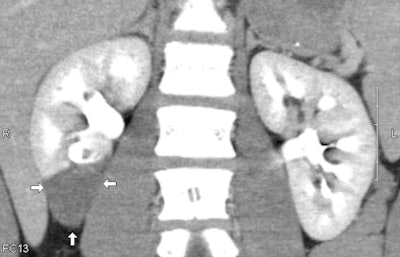

![]() |

| Devascularization of lower pole of right kidney: Coronal reconstruction image of contrast-enhanced CT scan of the abdomen of a 13-year-old male ATV rider. He was struck by a car and presented with hematuria. The image shows devascularization of the lower pole of the right kidney as indicated by arrows. |